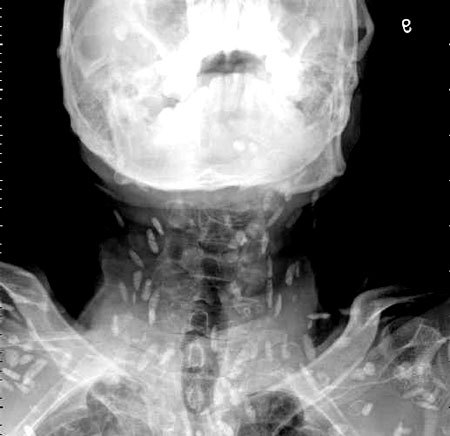

엑스레이를 찍어보니, 온몸에 촌충 같은 기생충이 퍼져있는 것이 Xray사진에 찍혔다.

기침으로 인한 고통을 호소한 환자를 진료하던 의료진은 환자의 엑스레이 사진을 보고 경악했습니다. 엑스레이 촬영물에는 여러 마리의 촌충과 유충이 가득 찍혀있는 것이었습니다.